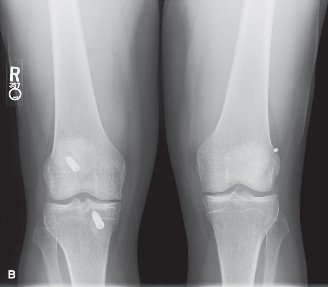

Standard weight-bearing radiographs, including anteroposterior (AP), lateral, Rosenberg (45-degree flexion posteroanterior), and Merchant views, are mandatory to assess bone stock, hardware placement, tunnel widening, and early degenerative changes.

The AP radiograph reveals metallic interference screws in both the femur and tibia. The tibial tunnel aperture appears significantly widened. Tunnel widening, or osteolysis, is a frequent complication in allograft reconstructions, driven by a combination of mechanical micromotion (the "bungee cord" and "windshield wiper" effects) and biological factors, including an exaggerated local cytokine response to the foreign allograft tissue and synovial fluid ingress into the bone tunnels.

The lateral radiograph is critical for evaluating tunnel position. In this patient, the femoral tunnel is noted to be placed anteriorly and vertically, high within the intercondylar notch. This vertical placement is a classic hallmark of the traditional transtibial drilling technique, which often sacrifices anatomic femoral footprint placement to accommodate the rigid trajectory of the tibial tunnel. A vertical graft effectively resists anterior tibial translation (Lachman) but fails utterly to resist internal rotation, leaving the patient with persistent rotatory instability (positive pivot shift).

A fine-cut Computed Tomography (CT) scan with 3D reconstructions is the gold standard for preoperative planning in the revision setting. The CT scan precisely quantifies the degree of tunnel widening and the exact spatial orientation of the existing tunnels. In this patient, the CT demonstrates a tibial tunnel that has expanded to 16 millimeters in diameter, with significant cystic changes extending into the metaphyseal bone.

The finding that most strongly favors a staged revision is tunnel widening. When existing tunnels expand beyond 14 millimeters, as seen in our patient's CT scan, achieving reliable, rigid aperture fixation of the new graft becomes biomechanically impossible. The lack of circumferential bone-to-graft contact severely impairs biological incorporation. Vertical femoral tunnel placement, retained hardware, prior autograft use, and meniscal tears do not inherently mandate a staged approach, as these can typically be addressed or bypassed in a single surgical setting.